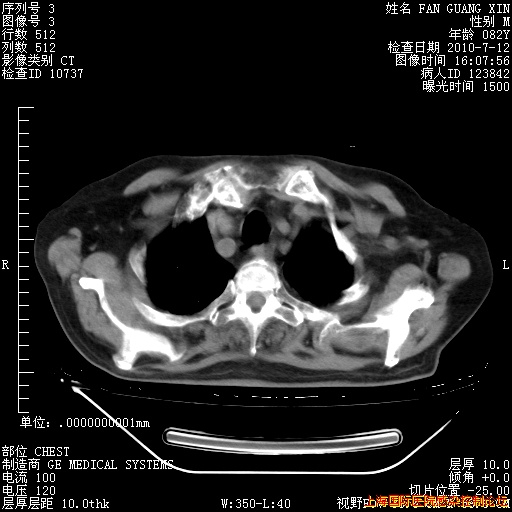

6月12日纵膈窗

整整相隔30天的肺部CT好像有所好转啊。甲强龙减量第3天,需要观察体温。

海管,自昨日你和我通完话后,不知您岳父消化道症状有无缓解?体温怎样?阅读7.12日胸部ct,个人认为目前激素治疗是有效的,甲强龙减量是适宜的。因在抗痨治疗,需密切观察肝功、肾功能和血常规。不过,老年、长期住院和大量使用激素,很担心菌群失调发生